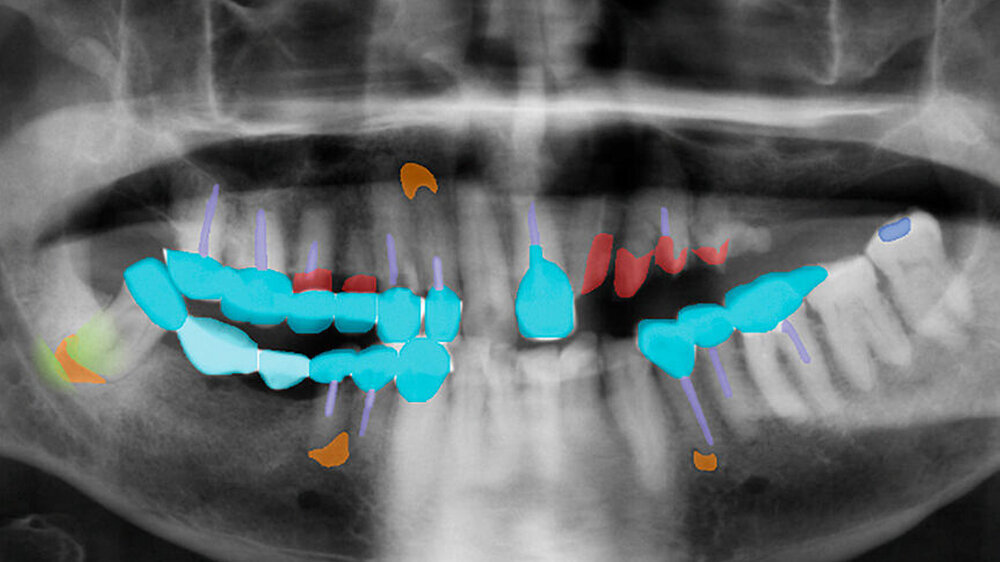

2. Schwierigkeit: Gerade für KI-Modelle in der Bildanalytik ist es zudem herausfordernd, kleinere Veränderungen, die nur wenige Pixel auf dem Bild betreffen, aufzuspüren. In vielen Fällen sind nur wenige Hundert Pixel auf einem mehrere Zehntausend Pixel großen Bild betroffen.

Forscher behelfen sich daher mit der Eingrenzung der relevanten Areale auf einem Bild: So kann Karies beispielsweise nur im Bereich der Zahnhartgewebe vorkommen, die meisten Zahnröntgenbilder weisen jedoch auch umfänglich andere Strukturen wie Knochen auf. Diese Areale auszublenden und dem KI-Modell nur den relevanten Bereich anzubieten, kann die Genauigkeit erheblich steigern.